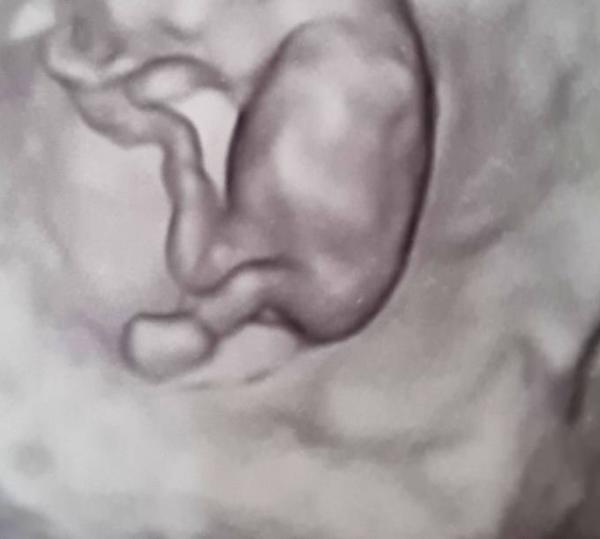

Meint ihr man könnte anhand dieser Bilder eine Tendenz abgeben, oder spasseshalber ein bisschen rätseln?

Bild zu 11.SSW 3D Ultraschall, Tendenz? - Schwanger - wer noch? Rund um die Schwangerschaft